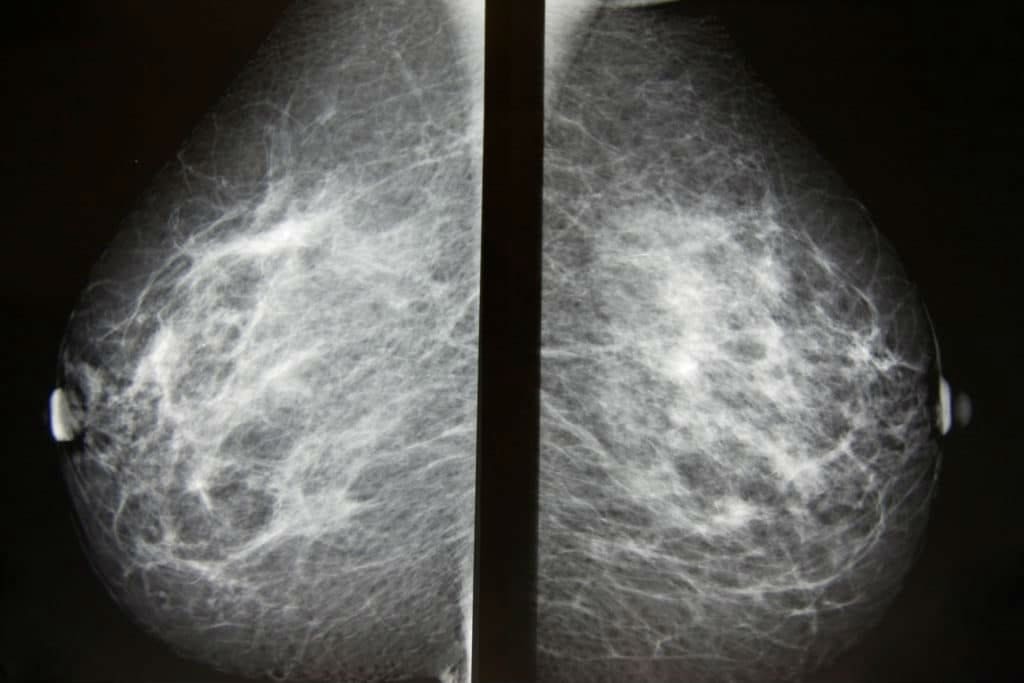

До 90% случаев болезней молочных желез возможно выявить с помощью УЗИ либо маммографии. Компьютерная томография (КТ) молочной железы нужна в качестве дополнительного метода исследования, без которого иногда невозможно поставить верный диагноз. Для проведения компьютерной томографии применяется томограф. Метод основан на действии рентгеновского луча, который пронизывает ткани органа и выполняет сканирование. Результат КТ отображается на рентгеновской пленке в виде ряда поперечных срезов.

Во время проведения томографии кушетка с лежащей на ней пациенткой медленно заходит в кольцо томографа. Длительность процедуры КТ обычно составляет не больше 30 минут. В течение процедуры пациентке нужно лежать, не двигаясь, это необходимо для получения наиболее достоверных результатов обследования. Рентгенологический излучатель томографа направляет лучи под разными углами, эти лучи имеют разную интенсивность. Все сигналы подаются на компьютер и на нем анализируются. Итоги диагностики в виде двухмерных срезов молочных желез выводятся на экран. Медперсонал при проведении процедуры находится в смежном кабинете.

— Магнитно-резонансная томография — не единственный метод исследования молочной железы. Можно ли сказать, что лучше — маммография, УЗИ или МРТ молочной железы?

Несмотря на высокую информативность МРТ, маммография и ультразвуковое исследование молочных желез – это скрининговые методы выявления рака молочной железы, они доступны более широкому кругу пациентов. Также, к примеру, при проведении МРТ невозможно выполнить прицельно-пункционную биопсию. Для контроля выполнения этой манипуляции используют аппарат УЗИ. То есть, можно сделать вывод, что все вышеперечисленные методы важны и подбираются в каждом случае индивидуально.